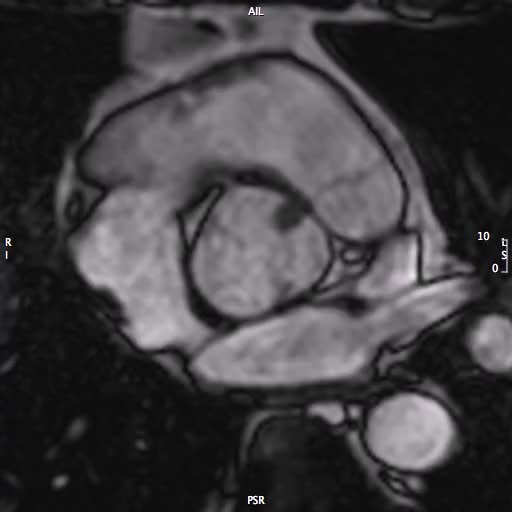

Infarto miocardico a coronarie indenni. Indicazione per RM, TC o entrambe?